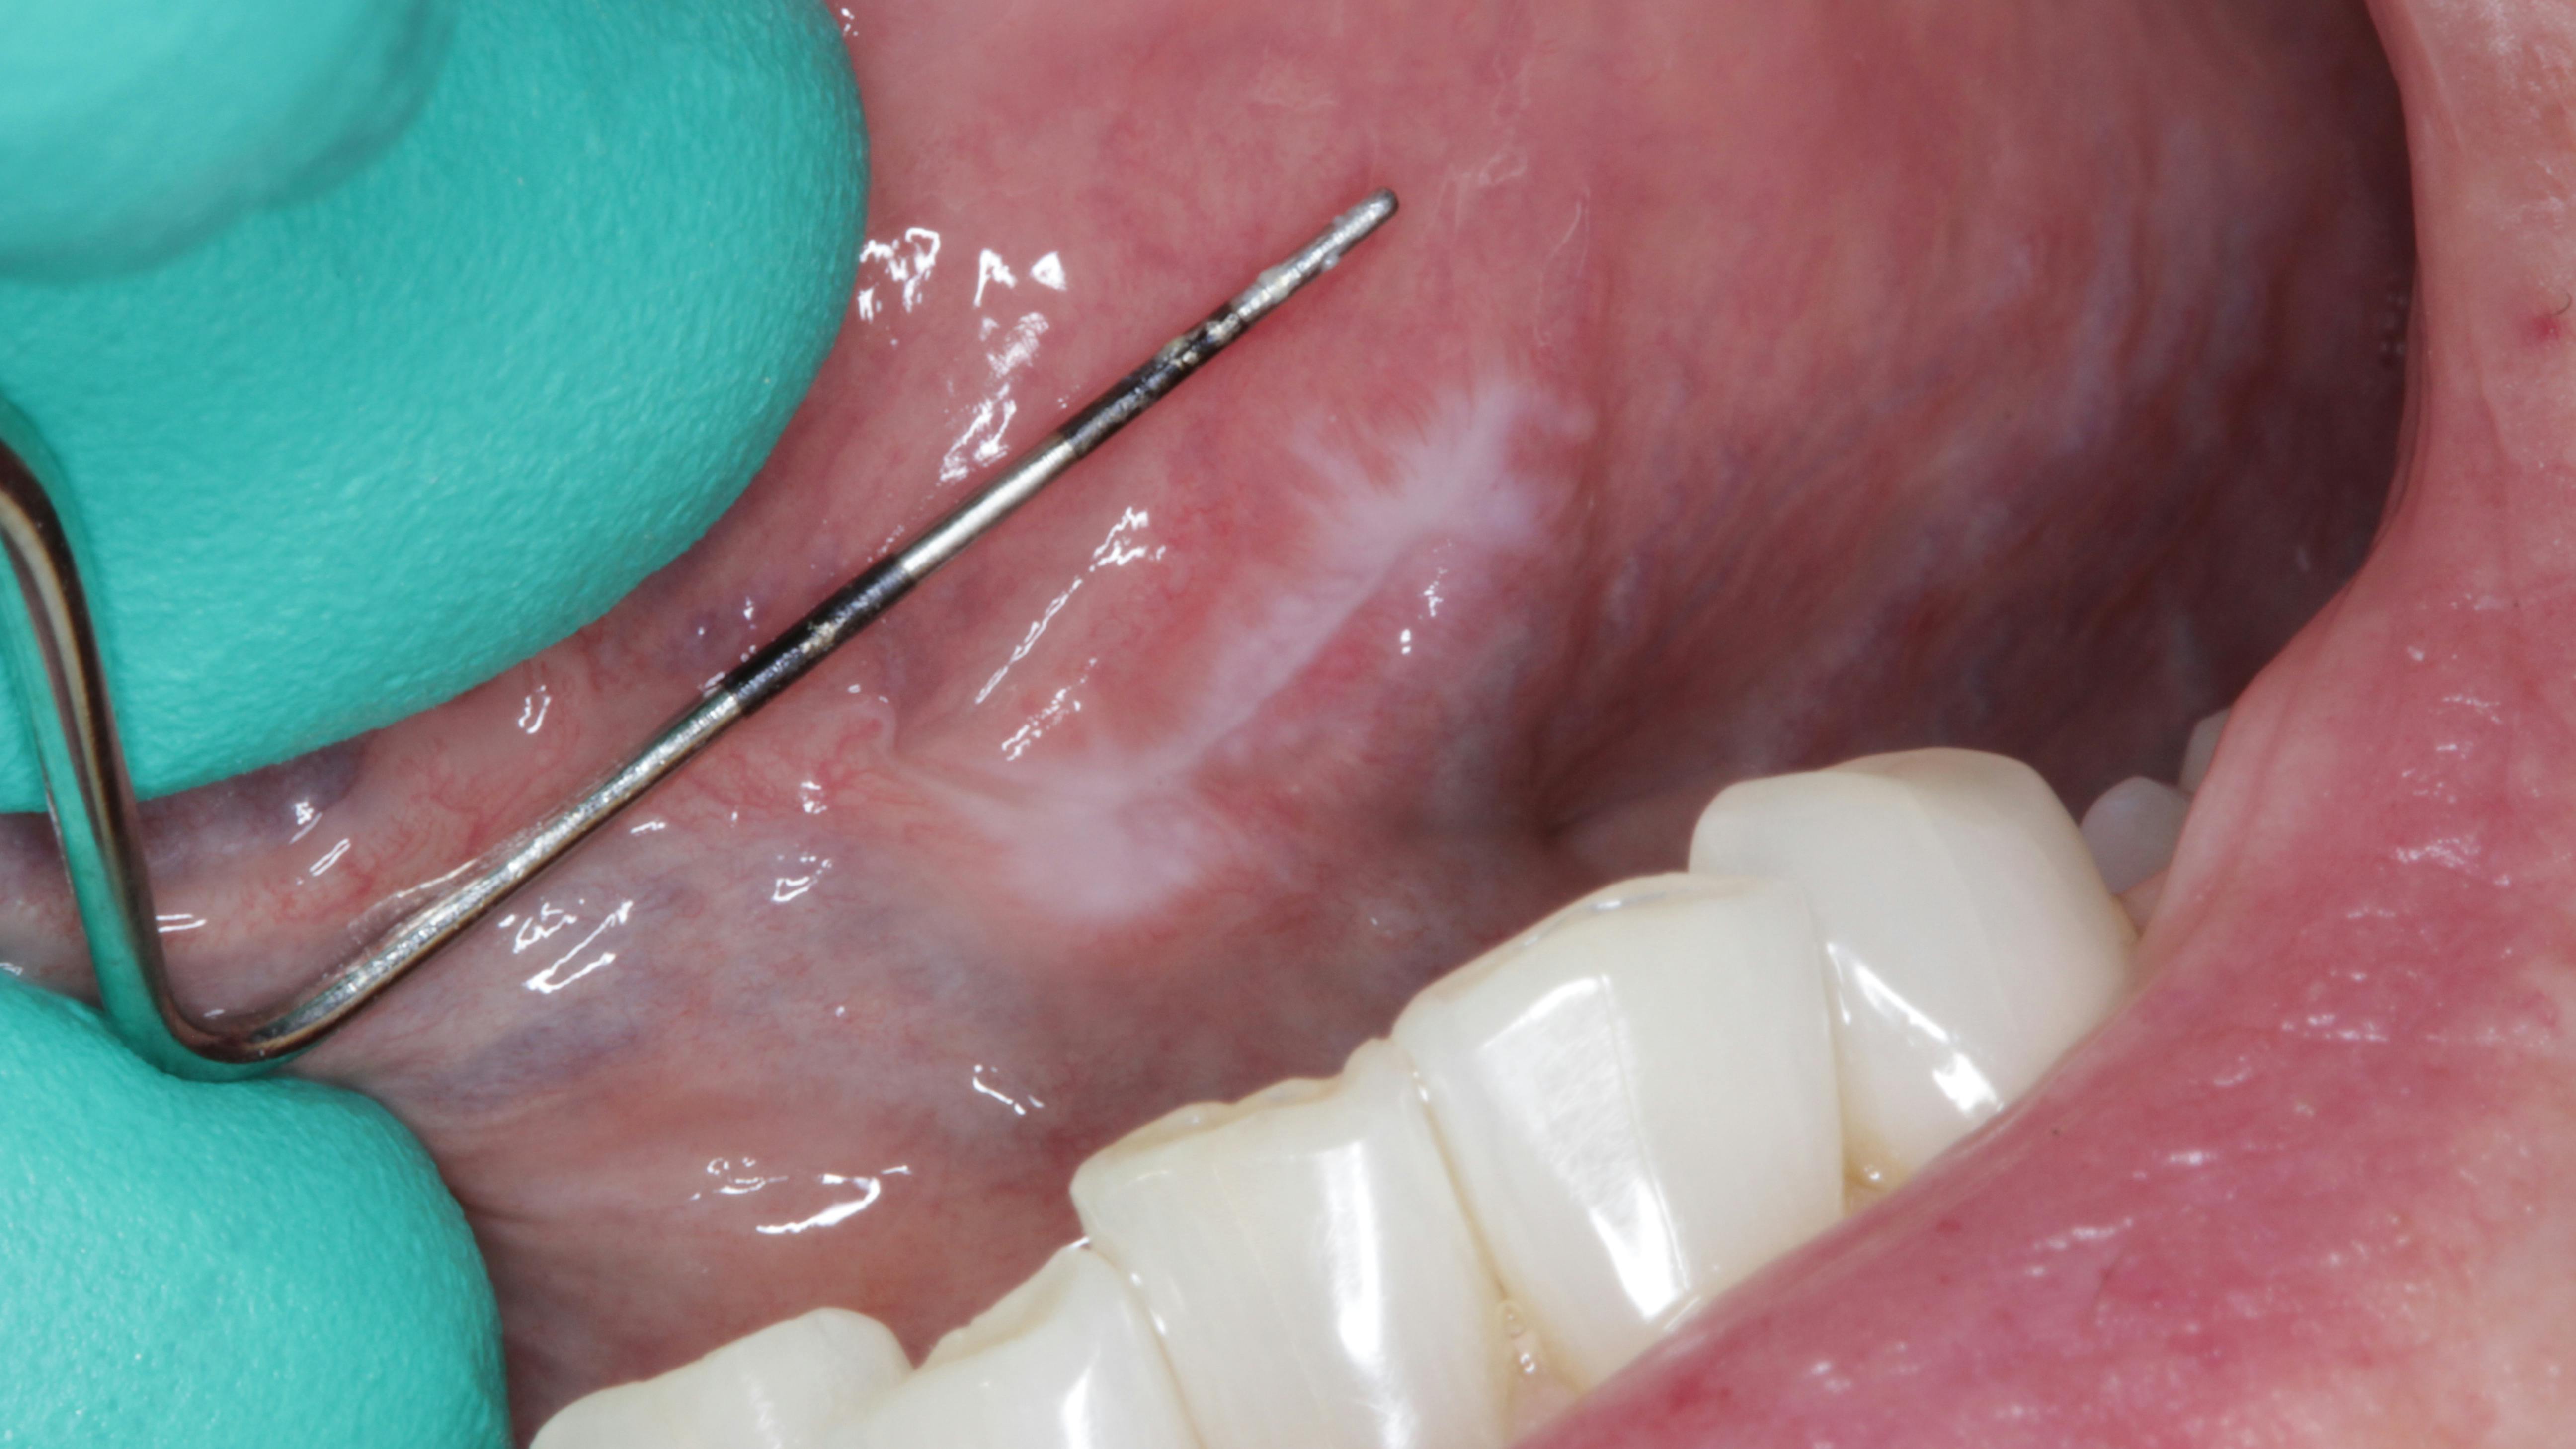

Discussion and likely diagnosis

The likely diagnosis in this case is oral mucocele, aka mucous retention cyst, from a blocked duct, secondary to chronic lip biting. It is hoped that the patient will eventually have a biopsy so a definitive diagnosis can be rendered. The patient's mom has been advised to be diligent in reminding her son to cease biting his lip.